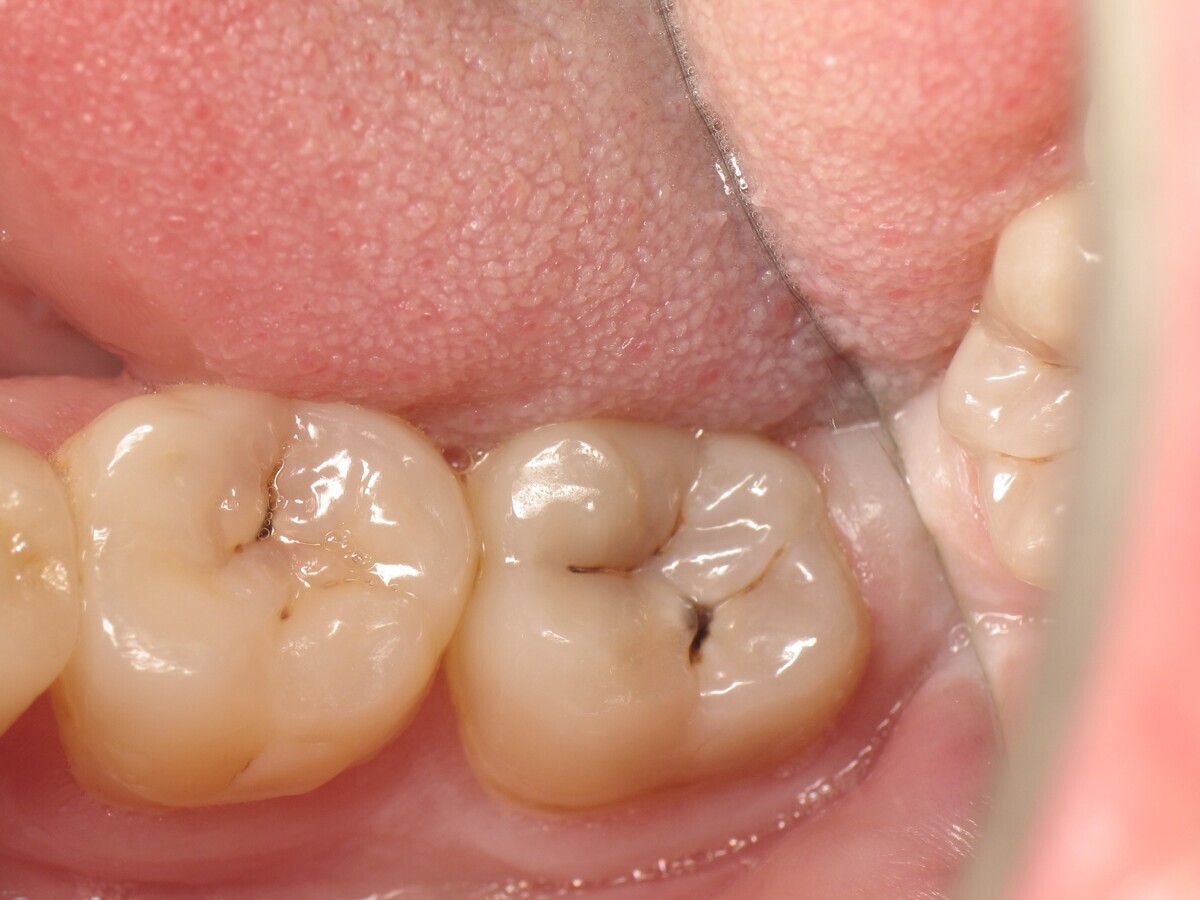

Este artículo describe el tratamiento de una cavidad clase I en un molar utilizando un composite termoviscoso mediante la técnica de la almohadilla (Figura 1). En primer lugar, se registran los detalles anatómicos utilizando una resina transparente, fluida y fotopolimerizable (Clip Flow, VOCO). El diente se aísla con un dique antes de aplicar el composite transparente a la superficie oclusal con un cepillo aplicador y fotopolimerizar durante 10 segundos (Figuras 2-4). La almohadilla oclusal así obtenida (Figura 5) debe almacenarse en alcohol (etanol o isopropanol) para eliminar la capa de inhibición. Luego se limpia la cavidad clase I (Figuras 6 y 7). A continuación se graba el esmalte durante 30 segundos y la dentina durante 15 segundos (Conditioner 36, Dentsply Sirona) y luego se enjuaga bien (Figuras 8 a 10). Debido al bajo espesor de la dentina remanente, también se aplica protección pulpar (Telio Desensitizer, Ivoclar Vivadent) (Figura 11). Luego se frota el adhesivo sobre las superficies dentales durante 20 segundos (Futurabond DC, VOCO), luego se seca bajo una pulverización de aire sin aceite graso durante 5 segundos y luego se fotopolimeriza durante 10 segundos (Figuras 12, 13). Para una humectación óptima, el fondo de la cavidad se cubre con un compuesto fluido de baja viscosidad (GrandioSO Light Flow, A3.5, VOCO) y se fotopolimeriza durante 20 segundos (Figuras 14, 15). Utilizando el Dispensador VisCalor, un dispensador portátil que permite el calentamiento y la aplicación simultánea de resinas, la cavidad se llena luego con un composite termoviscoso bulk (VisCalor Bulk, A2, VOCO).

Figura 01. Molar con caries clase I.